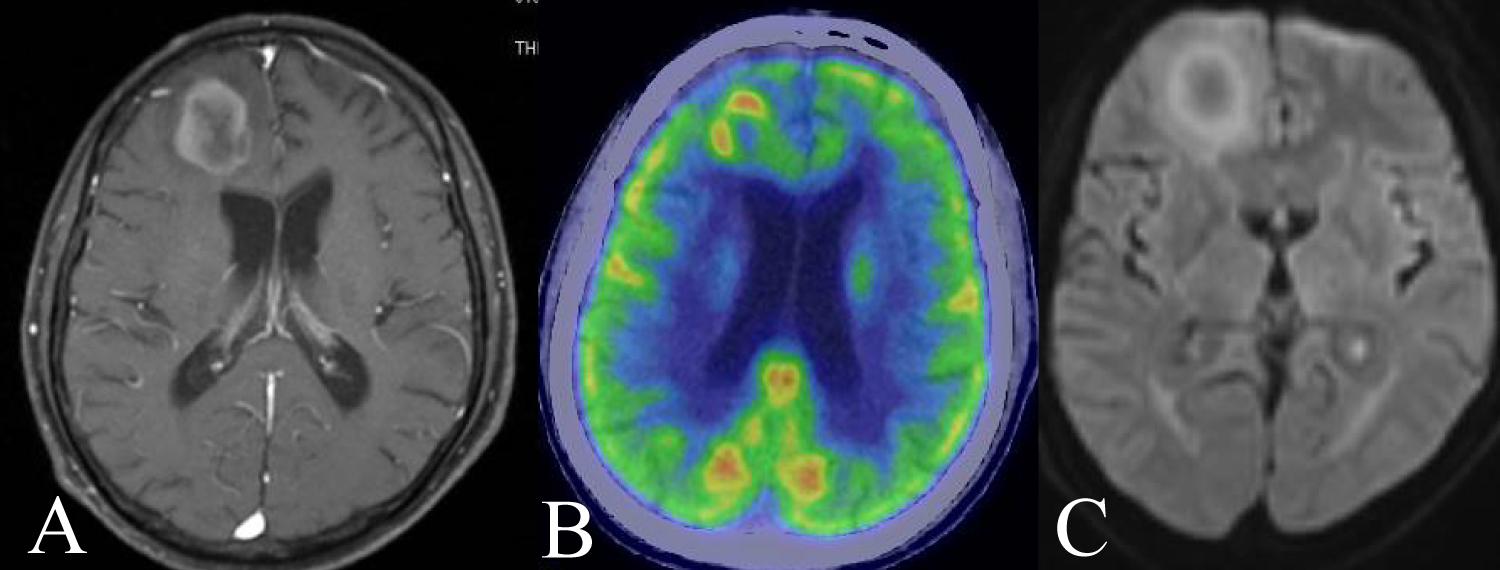

Case 6

28-year-old man presented dullness and we diagnosed his AIDS. His head MRI showed a ring enhancement at right caudate head (Figure 6A). FDG-PET showed ring like uptake and central low uptake at same lesion (Figure 6B). Histopathological findings were DLBCL. His CD4 positive T cell in number improved by combined ART, we performed rituximab plus high dose methotrexate therapy for him (Figure 6C). He survives at 84 months .

Figure 6: A 28 year-old man presented dullness. A) His head MRI showed a ring enhancement at right caudate head; B) FDG-PET showed ring like uptake and central low uptake at same lesion; C) DWI showed no clear findings. View Figure 6